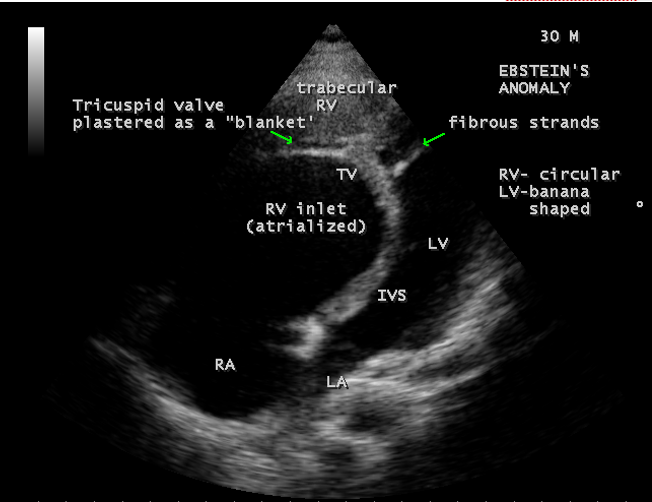

A 30-year old male was presented with marked cyanosis and no murmur and abnormal heart sounds on auscultation. 2D echocardiography revealed the features of Ebstein’s anomaly such as insertion of anterior leaflet into the trabeculated RV, forming a ‘blanket’ of leaflet tissue across the inflow and trabecular parts and bulging of ventricular septum towards leftward due to marked dilatation of RV, and LV became ‘banana’ shaped as shown in Figures 28 to 30.

Echocardiographic features Echocardiography is the diagnostic test of choice for Ebstein’s anomaly and the first echocardiographic diagnosis was reported by Lundstrom in 1969. The first diagnostic criteria for Ebstein’s anomaly using a multi-crystal two-dimensional system was defined by Hagan in 1974 [33] and they were able to recognize the apical displacement of the septal tricuspid leaflet and an elongated anterior tricuspid leaflet with increased excursion. The septal leaflet of the tricuspid valve attaches chiefly to the ventricular septum , but part of its basal attachment is to the posterior wall of the right ventricle [34] and it normally exhibits a slight but distinct apical displacement of its basal attachment to the central fibrous body compared to the mitral valve. The distal displacement of septal origin of tricuspid valve seems to be the best echocardiographic criterion as the characteristic sign for Ebstein’s anomaly and the degree of maximal displacement in normal hearts varies considerably with a mean difference of approximately 6 mm with mitral valve. To define the anatomic severity of Ebstein’s anomaly, four-chamber view is the best to demonstrate the apical displacement of septal tricuspid leaflet [35]. The ratio between the mitral-to-apex distance and the tricuspid-to-apex distance varies from 1 to 1.2 in normal subjects and 1.8 to 3.2 in patients and it is 3.6 as in Figure 18 with Ebstein’s anomaly. The true distance in the level of insertion of atrioventricular valves is obtained by substracting the tricuspid-to-apex distance from the mitral-to-apex distance with a mean value of 27.25 ± 12 mm in patients with proven Ebstein’s anomaly and it is 60 mm as shown in Figure 18 compared to reference group (5.7 ± 2 mm). Kambe and coworkers calculated the distance between both atrioventricular valves directly as a mean value of 21 mm with a range of 14 to 32 mm [36]. A maximum difference in the level of valve insertion of >15 mm in children and >20 mm in adults is discriminated between normal and Ebstein’s anomaly [37],[38]. Despite this fact, a patient with an ‘unequivocal’ Ebstein’s malformation can be encountered in whom the diagnosis cannot be made with certainity solely on the basis of apical displacement of the septal tricuspid valve leaflet. Occasionally, the leaflet attaches to the trabecular part rather than the inlet part of the septum, the conventional four-chamber view will not reveal any septal insertion as shown in Figures 28 and 29.

The anterior tricuspid leaflet is not involved in the process of downward displacement, it may be abnormally inserted occasionally and Shiina, et al documented the apical displacement of anterior tricuspid leaflet in 14% of cases echocardiographically [39]. The anterior leaflet forms a large, sail-like intracavitary curtain as in Figures 14, 25 and contains muscular strands instead of consisting entirely of a fibrous membrane as in the normal tricuspid valve [40]. It is potentially mobile with a brisk sail-like movement as shown in Figure 21 to 24 [41], free bloating with a ‘whipping motion’ across the right ventricular outflow tract (RVOT) as shown in Figure 26 and in some cases, the movement is restricted due to its adherence to the ventricular wall as in Figure 1 and 2, 4 and 9. It is often fenestrated, may in part be musculaized , inserting into the trabeculations of the right ventricle (RV) as in Figure 28 and rarely, the anterior leaflet forms an ‘atretic’ membrane that spans the midportion of the right ventricular cavity as in Figure 16.

In severe cases, the inferior wall of the right ventricle may consists soley of thin fibrous tissue, devoid of myocytes and thereby represent an area of aneurysmal dilatation as in Cases 2 (Figure 8) and 3 (Figures 20 and 24). It is apparently due either to slippage of right ventricular inflow tract away from the right atrioventricular junction or to focal excessive ‘undermining’ to myocardium, transmurally to the level of epicardium. A large atrialized area causes a severe reduction in the volume of the right ventricular pumping chamber and usually produces an abnormal configuration of muscular interventricular septum, which bulges leftward and thereby compresses the left ventricular chamber, resulting in reversal of ventricular shapes with a ‘circular’ right ventricle and a ‘banana’ [42] or ‘crescentic’ [43] left ventricle as shown in Figures 29 and 30 Thus, the proximal component of the right ventricle, the ‘inlet portion’ is the part directly involved with the malformation and the distal apico-trabecular and outlet portions that constitute the ‘functional right ventricle’, which is not involved and may be of normal size, but usually markedly diminished in dimensions and in some cases, it is dilated and thin walled.